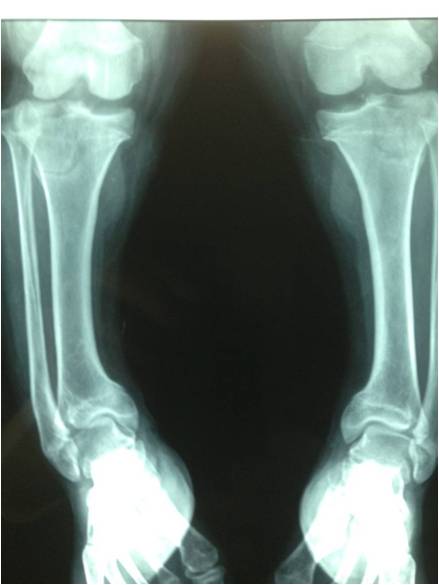

Blount disease is a developmental disorder characterized by disordered growth of the medial aspect of the proximal tibial physis resulting in progressive lower limb deformity. The deformity consists of varus, procurvatum, and internal rotation of the tibia, However, in the advanced stage of the disease, there is a bony bridge formation with medial plateau depression, joint instability, and leg length inequality, all of which have to be addressed by the proposed treatment. We treat this case by intra atticular osteotomy to elevation of medial plateau and another metaphyseal osteotomy to correct the varus and internal rotation deformities.

داء بلونت يطلق علي اعوجاج الساق المكون من هبوط باعلي الجزء الداخلي من اعلي عظمه الساق مع اعوجاج انسي بالساق و يتم علاج تلك الحالات بواسطه شقين عظميين احدهما خلال غظروف اعلي عظمه الساق والاخر بالجزء العلوي للساق مع الاستعدال التدريجي بواسطه مثبت خارجي مع العلم ان العلاج لا يرتبط بوزن المريض حيث يتم عمل العمليات بنجاح في الحالات السمنة الشديدة كما هو موضح بالصور